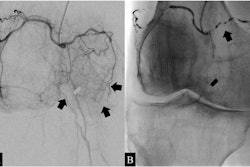

Grad-CAM interpretation of deep-learning-binary predictions. Grad-CAM heat mapping showing areas of highest activation for a control and case prediction made on the knee DEXA images. The regions of the map with the darkest color (purple) represent areas that were less informative in the prediction, while lighter colors (yellow) indicate regions of the image that informed the "case" or "control" prediction the most. We find areas of highest activation are most often on the medial side of the knee joint. Image courtesy of npj Digital Medicine through CC BY 4.0.The researchers then trained the AI model to identify these image-based phenotypes on a separate dataset of 546 images that had been independently annotated by three board-certified orthopedic surgeons. Next, in a test dataset of 110 images, the deep-learning model identified the imaging phenotypes with a sensitivity of 82% compared with clinicians (77%) and a specificity of 95% compared with the clinicians (97%).